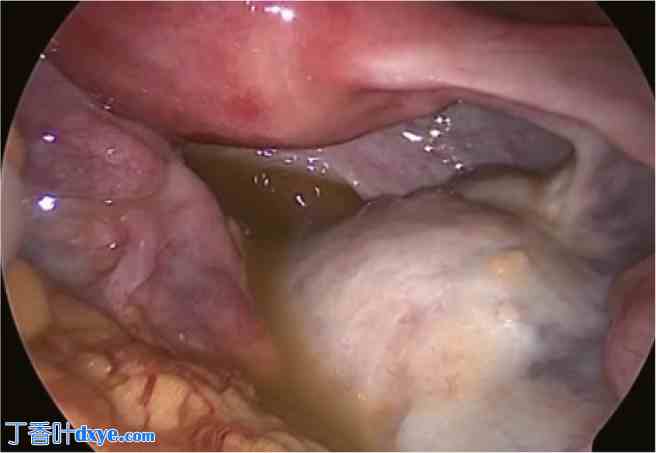

图 3

腹腔镜手术中的右侧卵巢畸胎瘤。

腹腔镜检查发现右侧卵巢畸胎瘤,并伴有黄色浑浊腹水。右侧附件未扭转或破裂。(有关此图例中颜色含义的解释,请参阅本文的网络版本。)